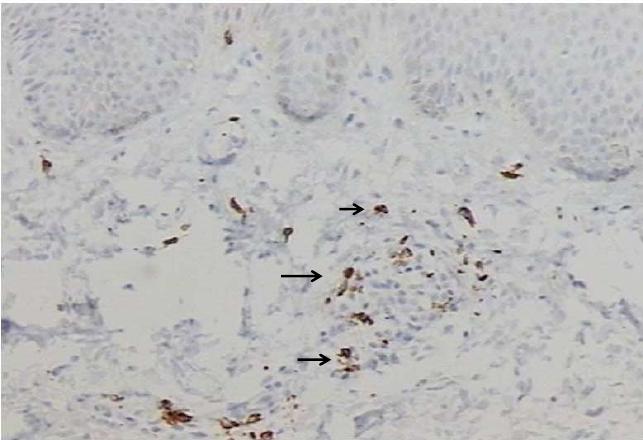

CD57 Ausente 1 12,5 3 33,3 1 25,0 0,2498

Raras 4 50,0 1 11,1 0 0,0

Leve 3 37,5 5 55,6 3 75,0

Total 8 100,0 9 100,0 4 100,0